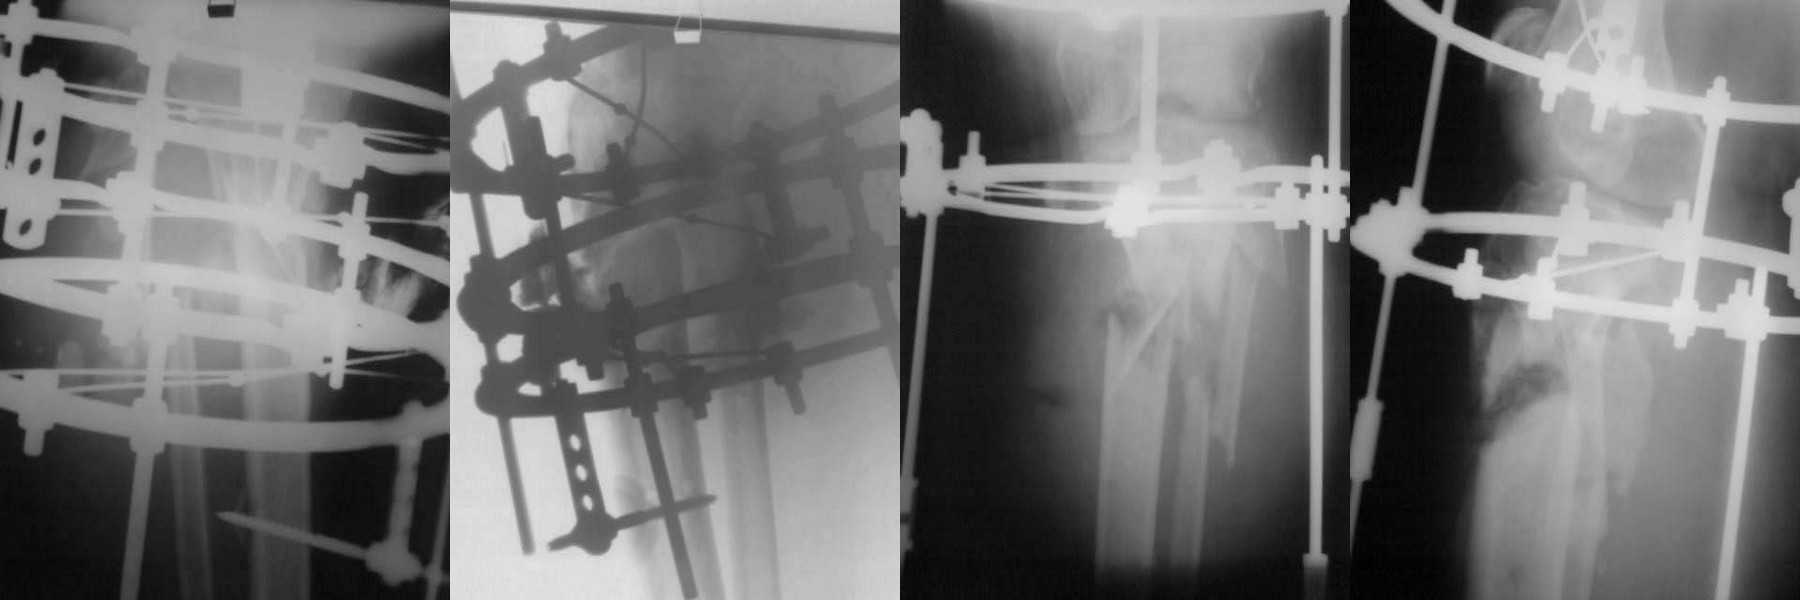

Перенесла несколько операций в условиях ЦРБ и краевой больнице. В настоящий момент у больной имеется несросшийся многооскольчатый перелом обеих костей правой голени, хронический остеомиелит, свищевая форма нейропатия малоберцового нерва справа. 04.02.2010г. больной выполнен: перемонтаж аппарата внешней фиксации, иссечение свищей, секвестрэктомия, дренирование полости. Рана полностью не ушита – видна кость, дренаж удален на 5 сутки, из раны скудное геморрагическое отделяемое, грануляции вялые, местами фибрин, голень отечна (отек не увеличился и не уменьшился), околоспицевого воспаления нет, температура тела нормальная, в лабораторных анализах легкая анемия, лейкоцитоза и палочкоядерного сдвига нет, биохимия и моча норма, в посеве из раны в первом – St. Epidermidis, во втором роста бак. флоры нет. Планируется консервативное лечение до гранулирования раны, затем замещение костного дефекта аутокостью. Рану не решился сразу зашивать и замещать костный дефект, в виду имевшегося гнойного затека 4,0х2,0 см. С данной патологией встретился впервые. Прошу совета по тактике ведения больной. Смущает длительно сохраняющийся отек и вялое течение заживления. Фото досылаю.